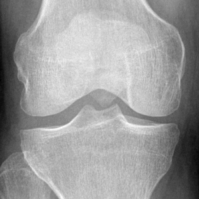

Refer to caption

Figure 6: A knee radiograph from the OAI database with the extracted knee joint in the red box (a). Obtained knee joint (b).

As shown in Fig. 6, as in [32], knee joints were detected using the learning model, YOLOv2 [33] and served as inputs of the proposed model. As a result of the preprocessing steps, 3,185 KL-0 and 2,126 KL-2 images were collected. According to each KL grade, the dataset was randomly divided into training, validation, and test sets with a ratio of 7:1:2, respectively.